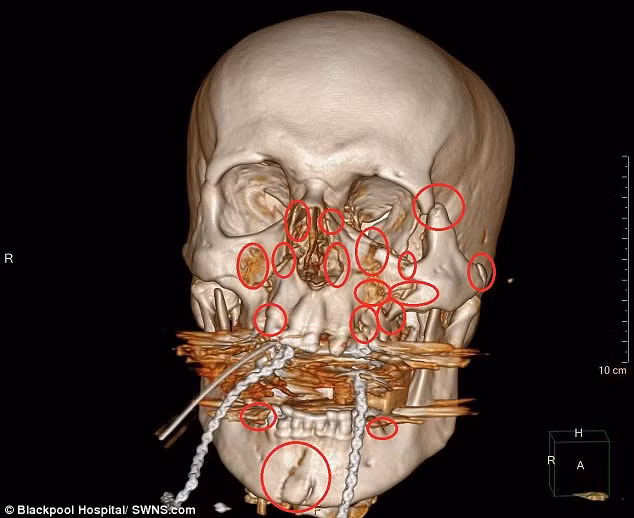

Andy không soi gương nên cũng không biết khuôn mặt mình đã kinh khủng như thế nào. Chỉ đến khi được xuất viện về nhà, anh mới được tận mắt xem tấm phim chụp X-quang hộp sọ, một mạng lưới dày đặc các mảnh kim loại và đinh vít mà bác sĩ đã dùng để có thể “sửa chữa” lại khuôn mặt của anh.

Dù phải mang trên mặt 13 mảnh kim loại và 52 đinh vít nhưng dấu hiệu đáng chú ý duy nhất anh cảm thấy sau khi trải qua cuộc đại phẫu mặt là âm thanh “tích” phát ra mỗi khi anh mở miệng. Tấm phim chụp khuỷu tay được cố định bằng đinh vít, nẹp kim loại và dây thép.